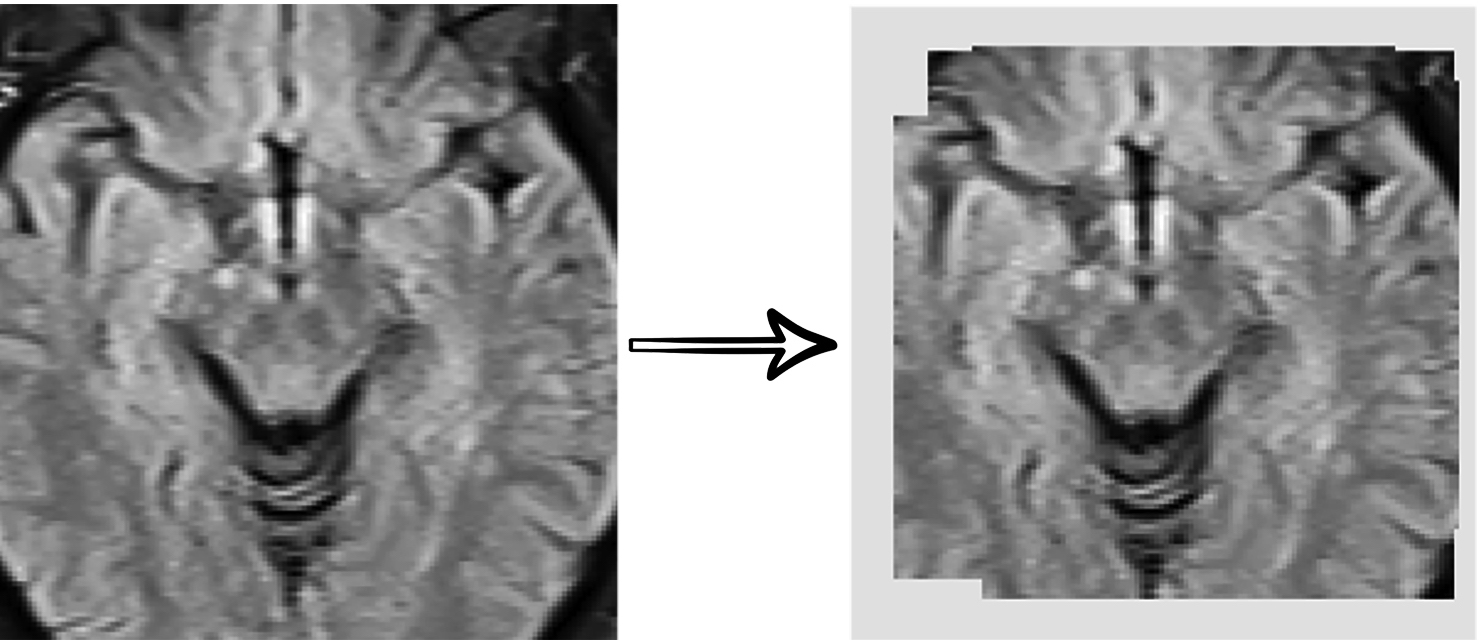

MRI is an imaging technique that consists of a patch of sequential sheared 2D images of organs from 3 different orientation terms with various scan setups, leading to volumetric data. The basic orientation terms for an MRI of the body taken are Saggital, Coronal, and Axial. The most common MRI sequences are T1-weighted and T2-weighted scans. A third commonly used sequence is the Fluid Attenuated Inversion Recovery (Flair). The Flair sequence is similar to a T2-weighted image except that abnormalities are brighter and normal CSF fluid is attenuated and made dark. This sequence is very sensitive to pathology and makes the differentiation between CSF and an abnormality much easier. The MRI data are classified into two groups of thick-slice and thin-slice data. In thick-slice MRI, the distance between sections is higher, and consequently, the number of slices is lower. Capturing thick slice MRI is faster, making the patient less exposed to radiation. Experts mostly use thick-slice data to diagnose diseases. Considering the severity of damaged areas of the brain and their confluence, each patient’s MRI is classified as follow: 0- absence, 1- punctuate foci, 2- smooth halo, and 3- large and irregular confluence areas of white matter changes in the brain (See Fig.5)